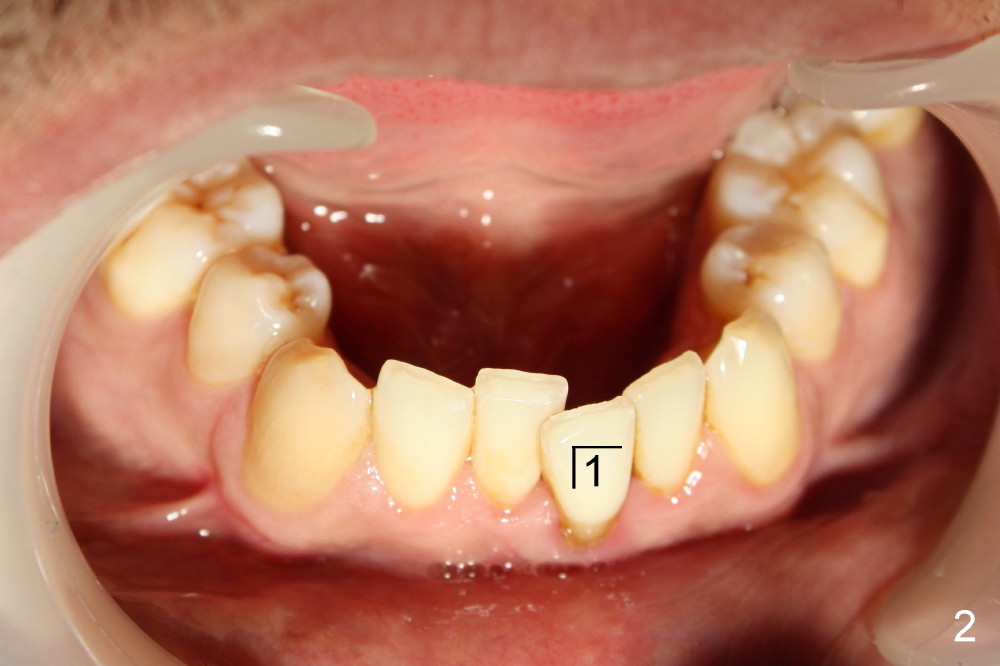

Forty-year-old man had ortho with extraction in his teens (Fig.1,2: B: bicuspid). Without wearing retainers, relapse occurs, particularly in the lower anterior. The lower left central incisor shifts labially with gingival recession (Fig.2,3). The attached gingiva is narrow for this incisor as compared to that of the neighboring tooth (Fig.4 between arrowheads). Although there is abundance of calculus, bone loss is mild to moderate (Fig.5-7). Scaling and root planing was finished today with schedule of perio maintenance every 3 months.

Both arches are narrow (Fig.1,2). Will be there space to move the lower left central lingually? Once the tooth is in normal position, gingival graft is performed to correct recession.